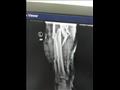

قال الدكتور أيمن رخا، وكيل وزارة الصحة بجنوب سيناء، إن المصاب وصل قسم الاستقبال والطوارئ بالمستشفى، عقب تعرضه لحادث طريق، وبتوقيع الكشف والفحص الطبي عليه، وإجراء الأشعة اللازمة تبين أنه يعاني كسرًا مفتوحًا "مضاعف" من الدرجة الثالثة بالساق اليسرى، مع تهتك شديد بعضلات مقدمة الساق مصحوب بضعف الدورة الدموية، وفقد جزء كبير من الجلد.

وأكد وكيل الصحة أن الفريق الطبي قرر إعداد المصاب للعمليات، لإجراء جراحة عاجلة لإنقاذ ساقه من البتر، وجرى تنظيف وتطهير الجرح المتهتك، ووضع المضادات الحيوية الموضعية، وإزالة الأنسجة التالفة، وتثبيت الكسر المضاعف بواسطة المثبت الخارجي، وسلك معدني للشظية. ​